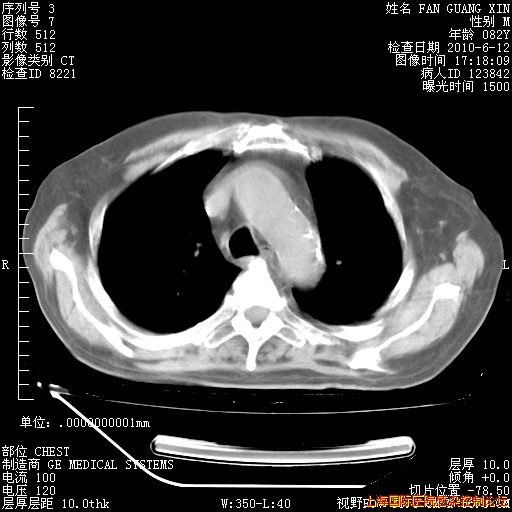

6月12日纵膈窗

整整相隔30天的肺部CT好像有所好转啊。甲强龙减量第3天,需要观察体温。

海管,自昨日你和我通完话后,不知您岳父消化道症状有无缓解?体温怎样?阅读7.12日胸部ct,个人认为目前激素治疗是有效的,甲强龙减量是适宜的。因在抗痨治疗,需密切观察肝功、肾功能和血常规。不过,老年、长期住院和大量使用激素,很担心菌群失调发生